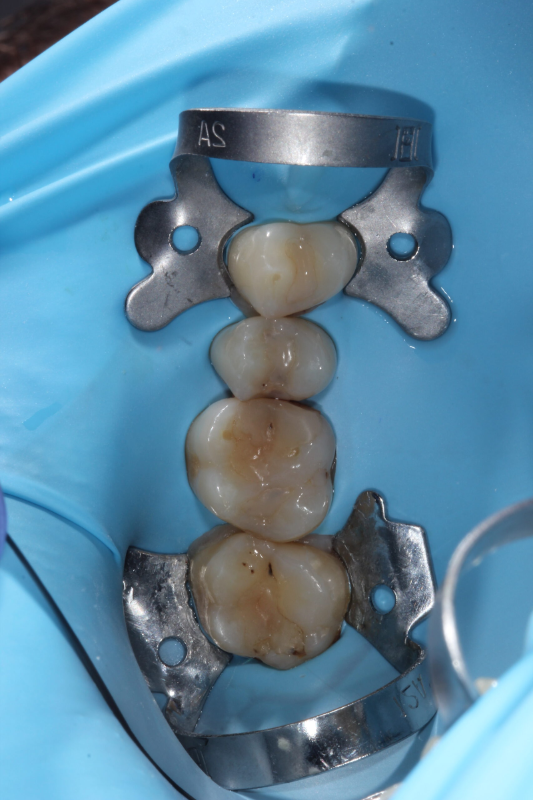

- Precizní čištění kanálků — pod mikroskopem, abychom nic nepřehlédli.

- Dezinfekce — důkladné odstranění infekce.

- Zaplnění kanálků — hermetické utěsnění speciálním materiálem.